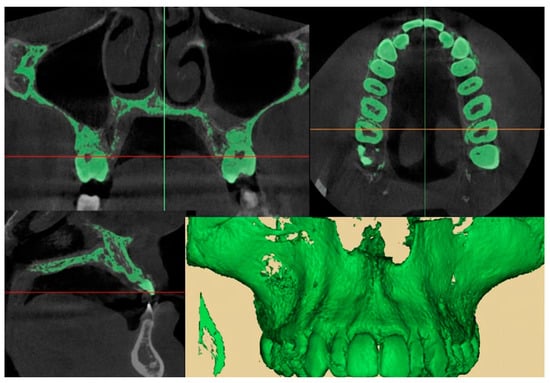

2.9.1. Qualitative Evaluation of Maxillary Expansion on Cone Beam Computed Tomography

3.2. Qualitative Evaluation of Maxillary Expansion on Cone Beam Computed Tomography

3.3. Quantitative Two-Dimensional Analysis of Upper Palatal Expansion on CBCT